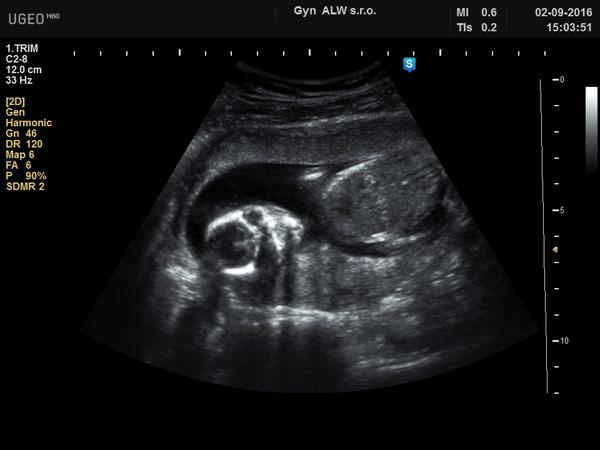

Poprosím Vás také o názor. Již 3x mi bylo sděleno, že se jedná o holku, ale tak 50/50, že to není jisté. Na velkém ultrazvuku ve 20 týdnu se nechtěl/a ukázat. No a dnes když jsem byla u doktora tak řekl, že to možná bude kluk že tam něco vidí, ale že prý obojí vypadá tak nějak stejně. Z videa, které mi nahrál zase nic není, má jen 7 vteřin, takže přikládám fotku z videa z 19 týdne. Doktor se mnou nekomunikuje, vždycky něco zahuhňá a tím to končí. Každý tady už ví co to bude a já pořád nevím na čem jsem ☹ Nemůžu si vychutnávat ani nákup výbavičky. Snad poslední "spása" před porodem bude ultrazvuk ve 30 týdnu, jinak už nevím.